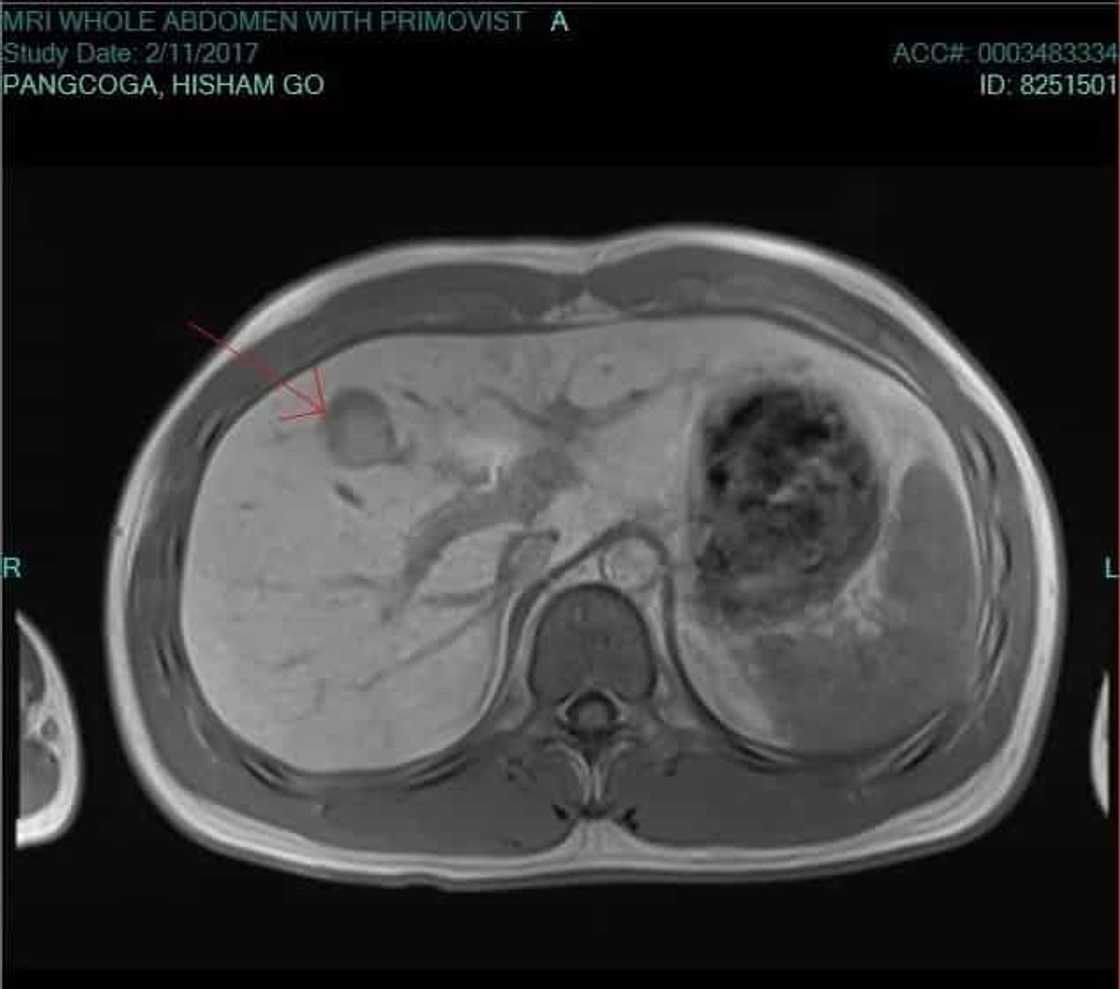

Hisham “Moi” Go is now fighting for his life after getting diagnosed with the same liver cancer that has already taken the lives of his two brothers.

The 27-year-old Hisham, the youngest of the three brothers, is now working in a financial firm. He was also recently diagnosed with the same deadly cancer.

“Doctors gave me 3 options as short term solution to the tumor: a surgery, RFA, and TACE. Each one has its own set of pros and cons. Each will cost me 3,000 - 4,000 USD (P150-200K) per session and I likely have to do it 2-4 times a year, depending on how aggressive the cancer is. The long term solution is to undergo liver transplant which costs 100,000 USD (P5M) if done in our local gov't hospital (PGH),” Hisham explained on his GoFundMe account.